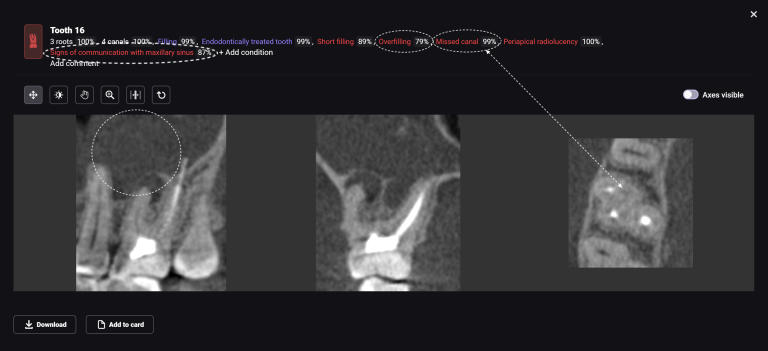

We present you a clinical case of planning implant treatment together with Diagnocat AI!